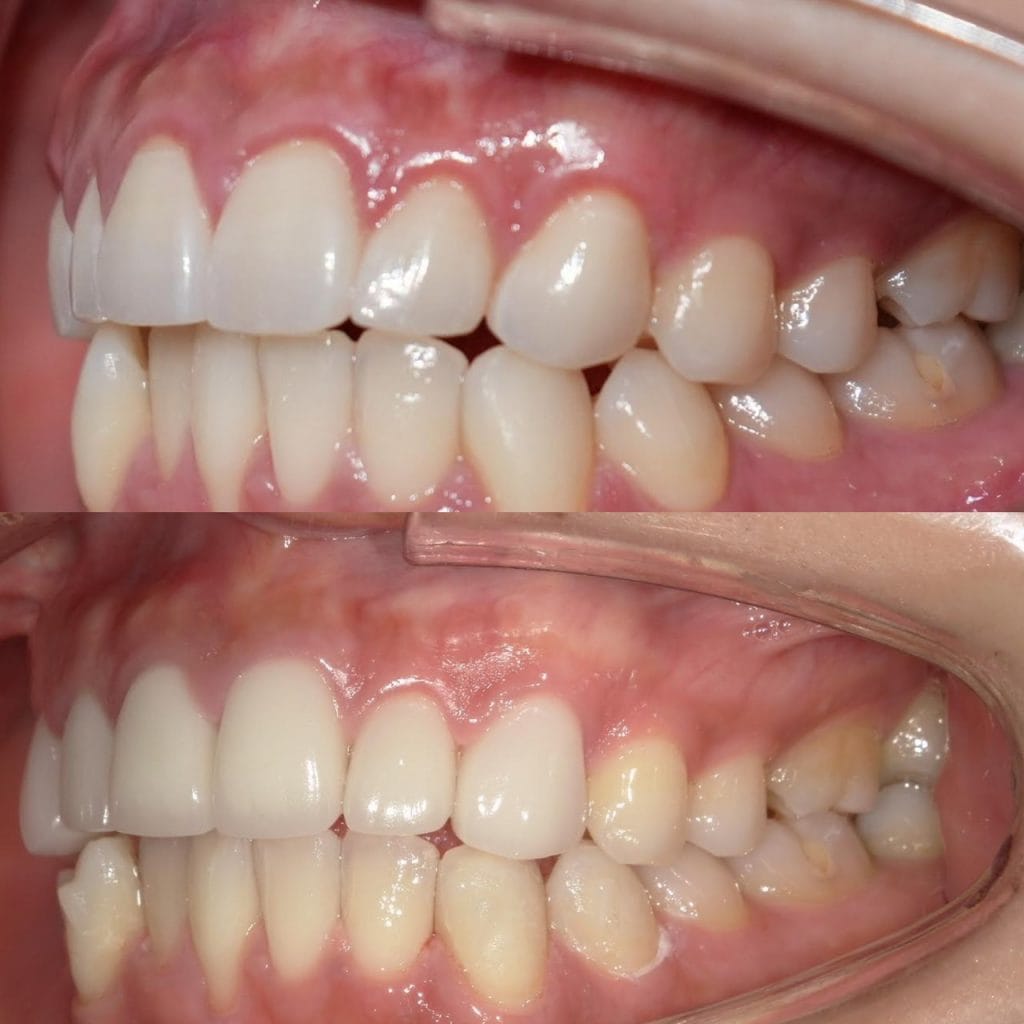

Case029

セラミック矯正の患者様です。

・上下の歯の入れ違い

・正中の歪みと隙間

を主訴にご来院くださいました。

この患者様は若年性歯周炎にかかってしまったため、一生懸命に歯を磨き、口の中は綺麗なのにも関わらず歯茎が下がってしまい、隙間が出来てしまっています。

これは矯正治療で歯の並び方を変えても絶対に無くなりません。

そのため、患者様の主訴を叶えるためにセラミック矯正で治療計画を練りました。

前のクリニックでは「上下一本ずつ抜糸してブリッジで矯正する」という計画だったようですが、

・患者様が非抜歯を希望されていること

・歯を抜かなくても綺麗に並べられそうだったこと

を理由に、当院では上は抜かずにセラミック。下は形態修正だけで対応しました。

この方針変更だけでもお値段も安く、また侵襲(ダメージ)を少なくすることができました。

治療の結果、最低限の侵襲で、見違えるほど綺麗な口元に治療することができ、患者様もとても喜んでくださいました。

主訴とご希望によって、ワイヤー矯正、マウスピース矯正、セラミック矯正のどの矯正が適しているかは異なります。

当院では上記全ての治療法に対応することができるので、主訴とご希望に沿った方法で治療することが可能です。

カウンセリングにてご希望をお伺いした後、一つ一つの治療の違い、当院のおすすめをご紹介いたしますので、ご希望の治療方法をお選びいただけます。

歯並びなどお口元にお悩みのある方、より綺麗な口元になりたい方はぜひ一度ご相談ください。

【主訴】

・上下で入れ違っている前から2本目の歯のすれ違いを治したい。

・清潔感のある白さで明るい綺麗な口元にしたい

・歯の隙間を無くしたい

【ご要望、ご状況】

・歯を抜かずに治したい

・前医では上下1本ずつ抜歯をして、ブリッジで上3本、下3本の計6本を治すことを提案された。

【今回の治療法】

・右上の犬歯から左の前歯までの計4本をジルコニアセラミックで治療

・色は自分の歯よりやや白いくらいでホワイトニングをしてもしなくても大丈夫なくらいの白さ

・歯は抜かない

・右下の歯は形態修正だけで対応

・歯茎のラインを歯肉整形術で整える